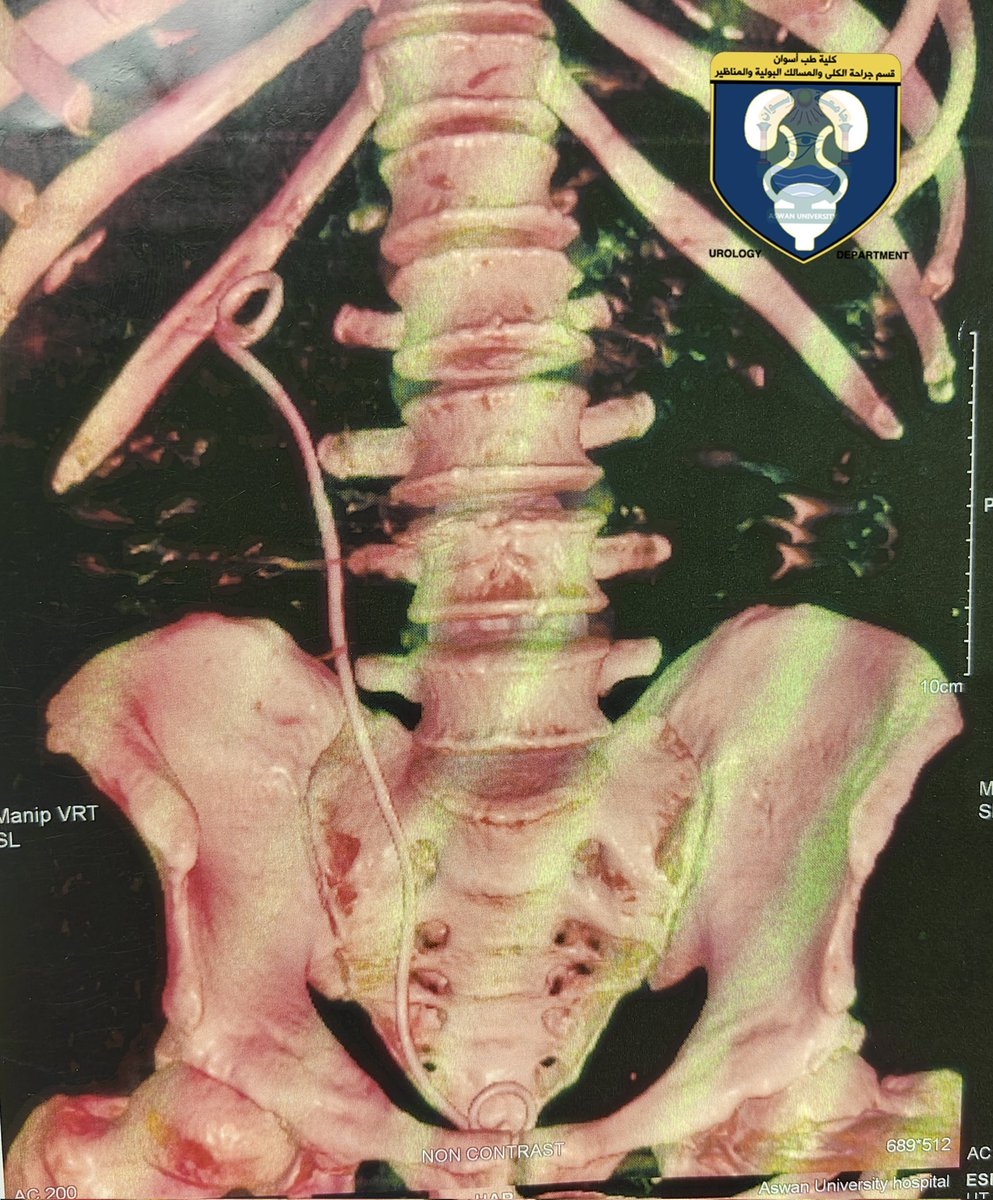

My rare case report was published

(Intracardiac migration of ureteral double-J stent)

1st case reported in Egypt

10th case reported all over the world